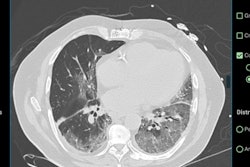

DetectedX was established to aid doctors and radiologists diagnose breast cancer, lung cancer, and COVID-19 faster and more accurately. Its online on-demand educational platform aims to improve radiological detection and is used by more than 3,000 users across 150 countries.